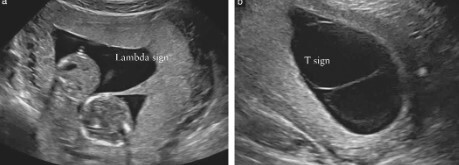

How can you differentiate a monochorionic pregnancy from a dichorionic pregnancy?

• T sign (monochorionic) vs twin peak sign (dichorionic)

What type of twin pregnancy?

Dichorionic diamniotic

Note: Arrow point to the twin peak sign (beak-like tongue between the two membranes of a dichorionic pregnancy).

Monochorionic diamniotic

Note: Arrow points to the intertwin membrane (T sign without twin peak sign).